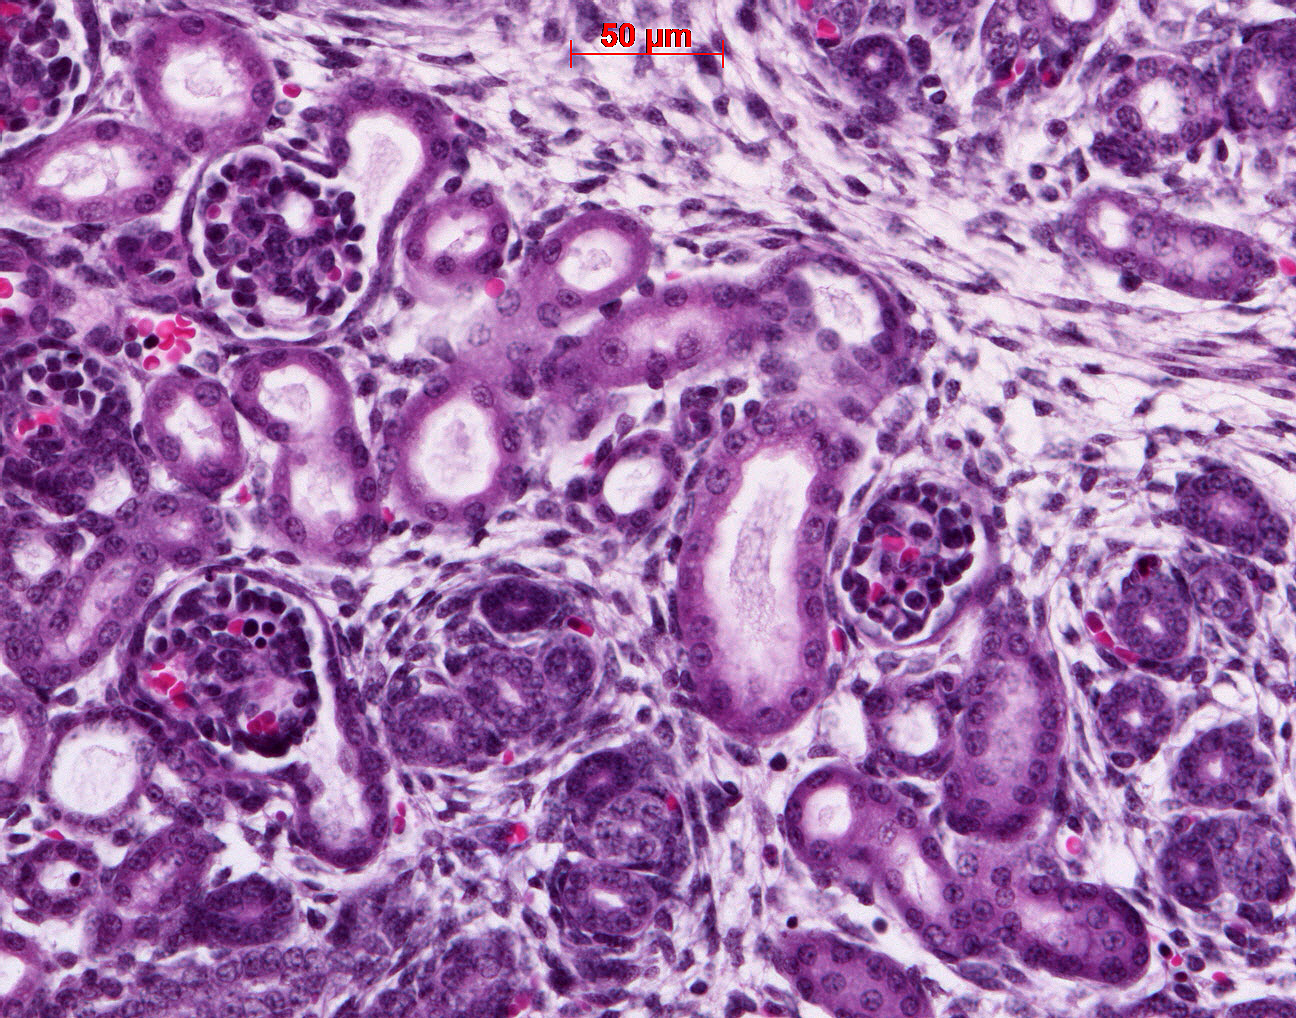

Caption Tubule dilation or mild cystic disease

Dctn5b2b315Clo dynactin 5; Bench to Bassinet Program (B2B/CVDC), mutation 315 Cecilia Lo

Dctn5b2b315Clo/Dctn5b2b315Clo C57BL/6J-Dctn5b2b315Clo